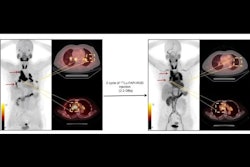

Costa and colleagues in a previous study found that radioligand therapy with Y-90-labeled inhibitors of FAPI was tied to promising tumor control in patients with sarcoma. The team’s protocol consists of a first-cycle administration of 3.7 GBq of Y-90Y FAPI-46 performed and adjusted in possible subsequent cycles.

For the study presented at SNMMI, the team’s research focused on absorbed dose calculations for lesions and organs at risk in patients receiving the first cycle of Y-90 FAPI-46 radioligand therapy.

The study included 17 patients who underwent three PET/CT scans of the kidneys and areas where tumors manifest. The patients were intravenously administered an average dose of 5.7 GBq. The researchers also derived lesion and kidney uptakes from PET/CT scans taken one, four, and 20 hours postinjection, respectively.

Based on these findings, the dosage received by organs at risk allows for multiple cycles of 90Y-FAPI treatment. He added that the scout activity evaluation provides valuable dosimetry data for further cycles, Costa noted.